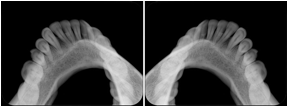

2 Occlusal Vertical Maxilla A Dental Image Layout

DL-C001A

Reference: DL-C001-U1L0

Reference: DL-C001-U2L0

2 Occlusal Vertical Mandible A Dental Image Layout

DL-C002A

Reference: DL-C002-U0L1

Reference: DL-C002A-U0L2

2 Occlusal Horizontal Maxilla A Dental Image Layout

DL-C003A

Reference: DL-C003-U1L0

Reference: DL-C003-U2L0

2 Occlusal Horizontal Mandible A Dental Image Layout

DL-C004A

Reference: DL-C004-U0L1

Reference: DL-C004-U0L2